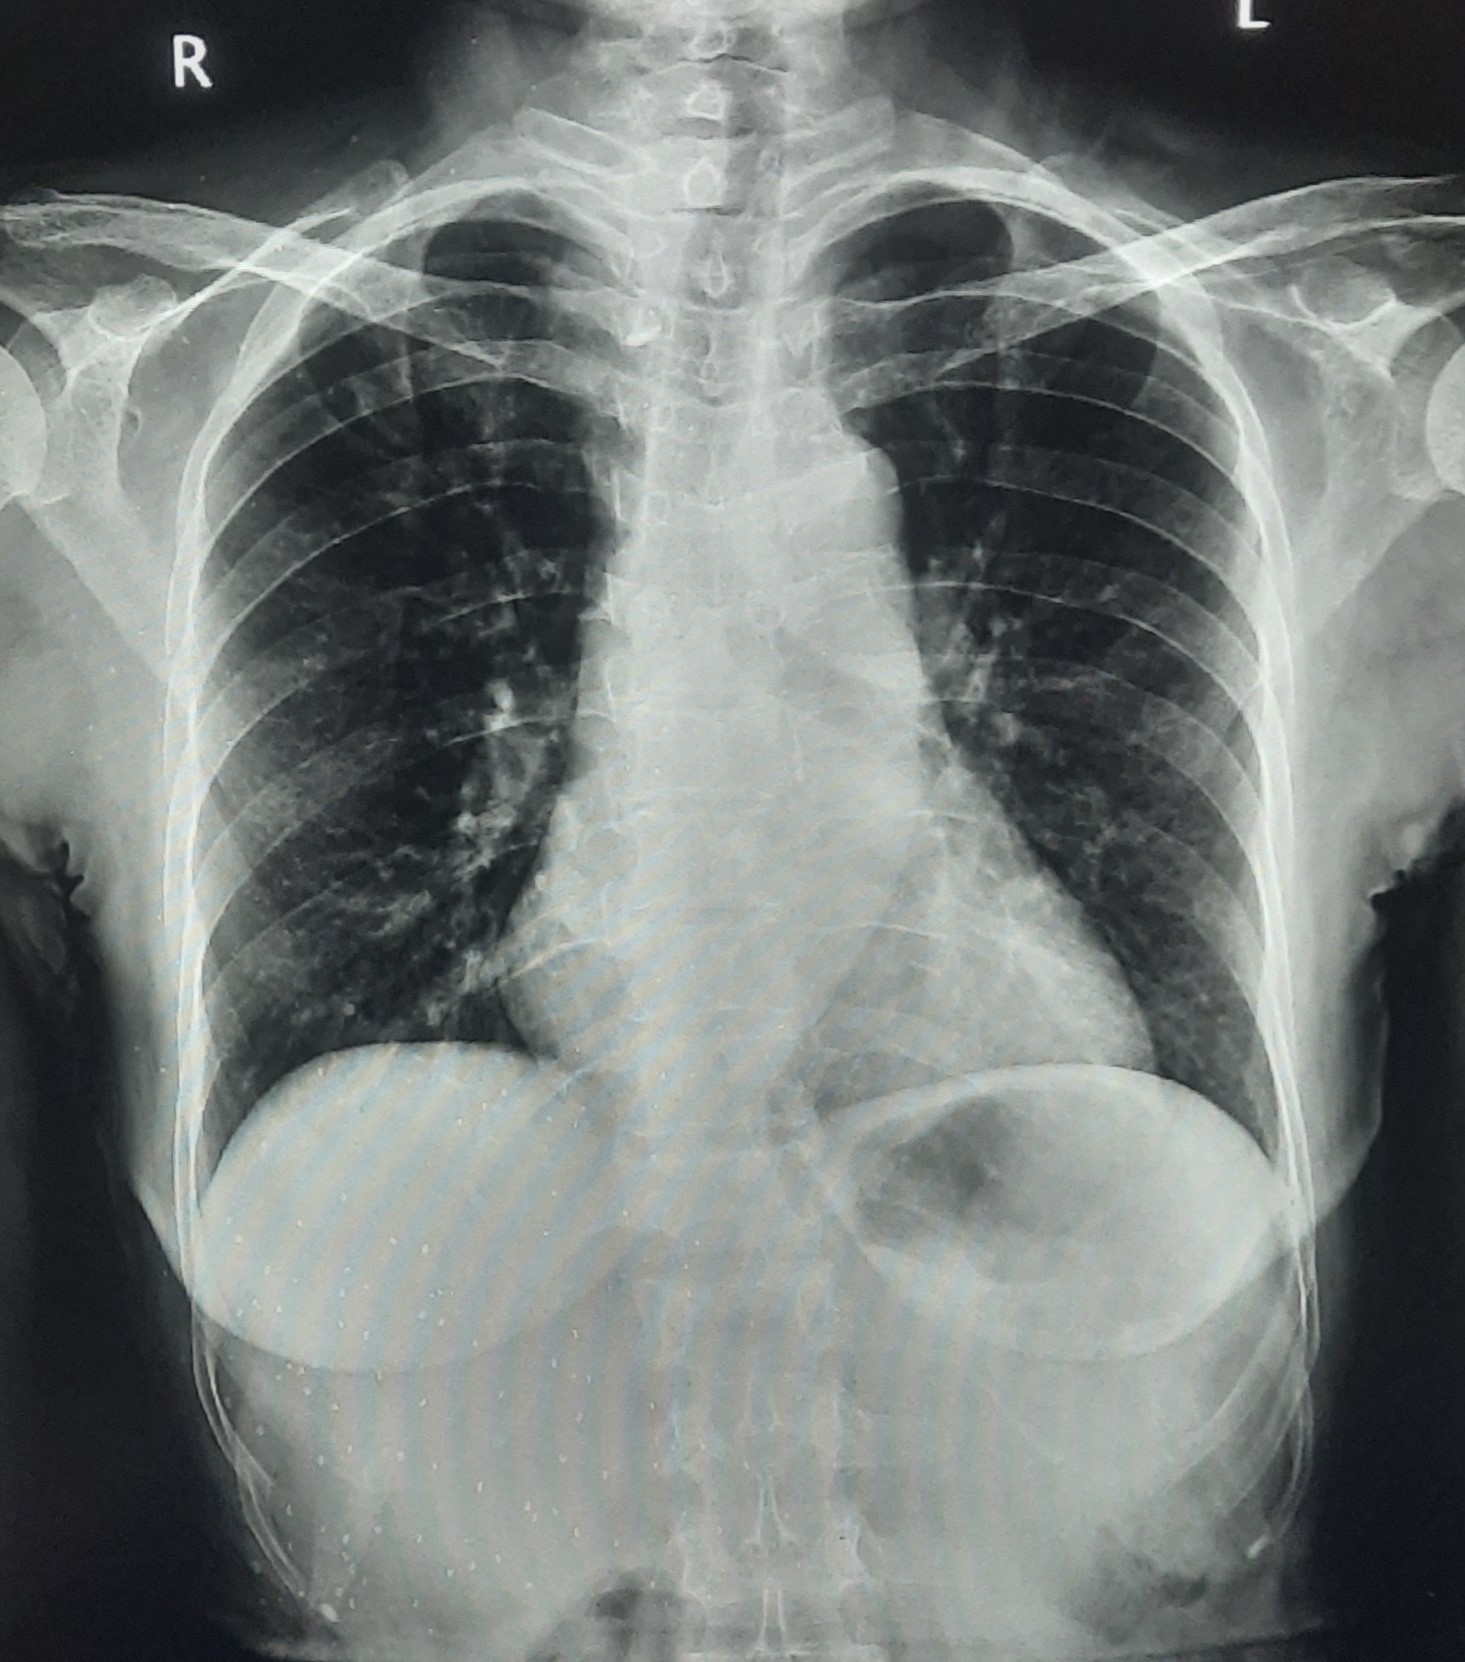

| 338 | IGGMC, Nagpur, Nagpur | P2 | 29-4134 | Rupesh Dongse | Consent taken on Paper | 43 Yrs. |

Provisional Diag : Consolidation

Final Diag : Bilateral Consolidation Community Acquired Pneumonia With Type 1 Respi Failure In Cronic Alcoholic |

Non-TB Case (Confirmed) | Bilateral Consolidation | Abnormality visible on x-ray |